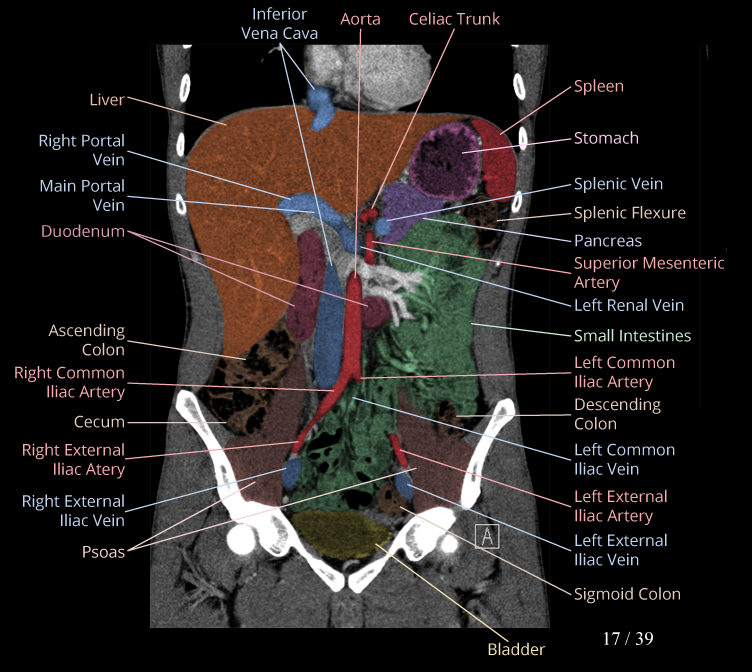

Body

Covers abdominal CT anatomy.